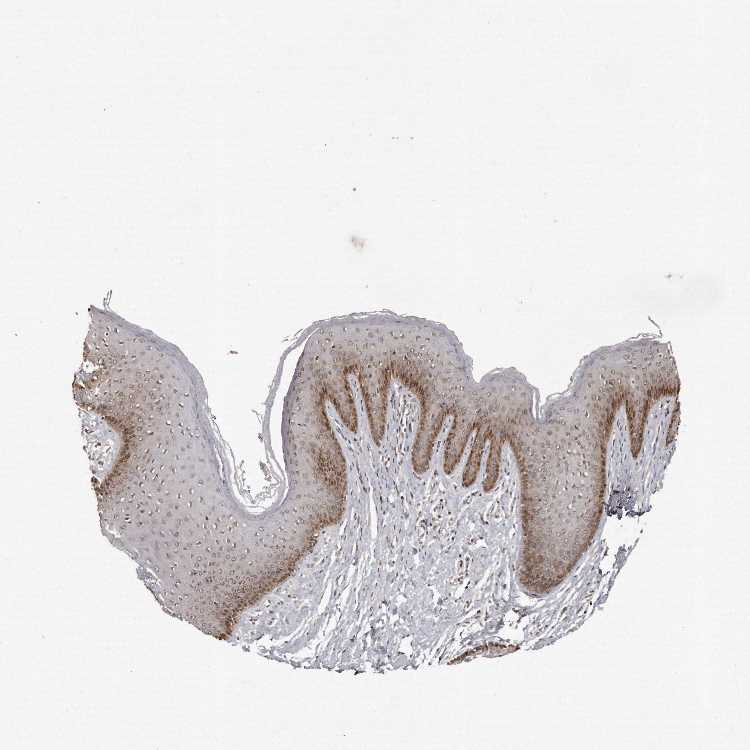

SKIN 2 - Antibody stainingi

Antibody staining in the annotated cell types in the current human tissue is reported as not detected, low, medium, or high, based on conventional immunohistochemistry profiling in selected tissues. This score is based on the combination of the staining intensity and fraction of stained cells.

Each image is clickable and will lead to virtual microscopy that enables deeper exploration of all samples and also displays staining intensity scores, fraction scores and subcellular localization as well as patient and tissue information for each sample.

Antibody HPA028612

Epidermal cells High